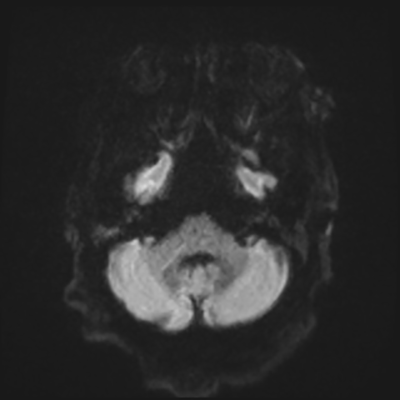

You come back the next day and see how things are going. The patient's electrographic record has shown a moderate encephalopathy (diffuse slowing, disorganization) with frequent right posterior quadrant delta slowing. Based on this result, and an adequately improved clinical examination, you give the okay to proceed with obtaining an MRI of his brain. This is shown below.

MRI brain (DWI)